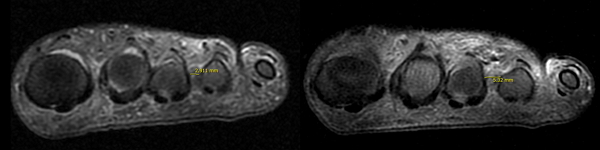

»çÁø ¼³¸í=¼ö¼ú Àü Á¼Àº ¹ß°¡¶ô »çÀÌ °£°Ý(ÁÂ) ¹× ¹Ì¼¼³»½Ã°æ À¯¸®¼ú ÈÄ ³Ð¾îÁø ¹ß°¡¶ô »çÀÌ °£°Ý(¿ì)

Áö°£½Å°æÁ¾ ¹Ì¼¼³»½Ã°æ À¯¸®¼úÀº ¼Õ¸ñÅͳÎÁõÈıº ³»½Ã°æ À¯¸®¼ú°ú ºñ½ÁÇÏ´Ù°í »ý°¢ÇÏ¸é µÈ´Ù. ½Å°æÀ» °¨½Î°í ÀÖ´Â Àδ븦 ÅÍÁ༠¹ß°¡¶ô »çÀÌ °ø°£À» ³ÐÇô Áõ»óÀ» ÇØ°áÇÏ´Â Ä¡·á¹ýÀÌ´Ù. ÇǺθ¦ ±æ°Ô Àý°³ÇÏÁö ¾Ê°í ³»½Ã°æ°ú ¼ö¼ú±â±¸°¡ ÁøÀÔÇÒ ¹Ì¼¼ÇÑ ÁøÀԷθ¸À¸·Î º´º¯ ºÎÀ§¿¡ Á¢±ÙÇϱ⠶§¹®¿¡ Àý°³·Î ÀÎÇÑ ÅëÁõ, ÃâÇ÷, ÈäÅÍ µî ºÎ´ã°¨Àº ÀÚ¿¬ÀûÀ¸·Î ÁÙ¾îµé°Ô µÇ¾ú´Ù. ¶ÇÇÑ ³»½Ã°æÀ¸·Î º´º¯ ºÎÀ§¸¦ Á÷Á¢ È®ÀÎÇÏ¸é¼ ¼ö¼úÀ» ÁøÇàÇÏ´Â ¸¸Å ÁÖº¯ Á¶Á÷ ¼Õ»ó ¾øÀÌ Á¤È®ÇÏ°í ¾ÈÀüÇÑ ¼ö¼úÀÇ ÁøÇàÀÌ °¡´ÉÇÏ´Ù.